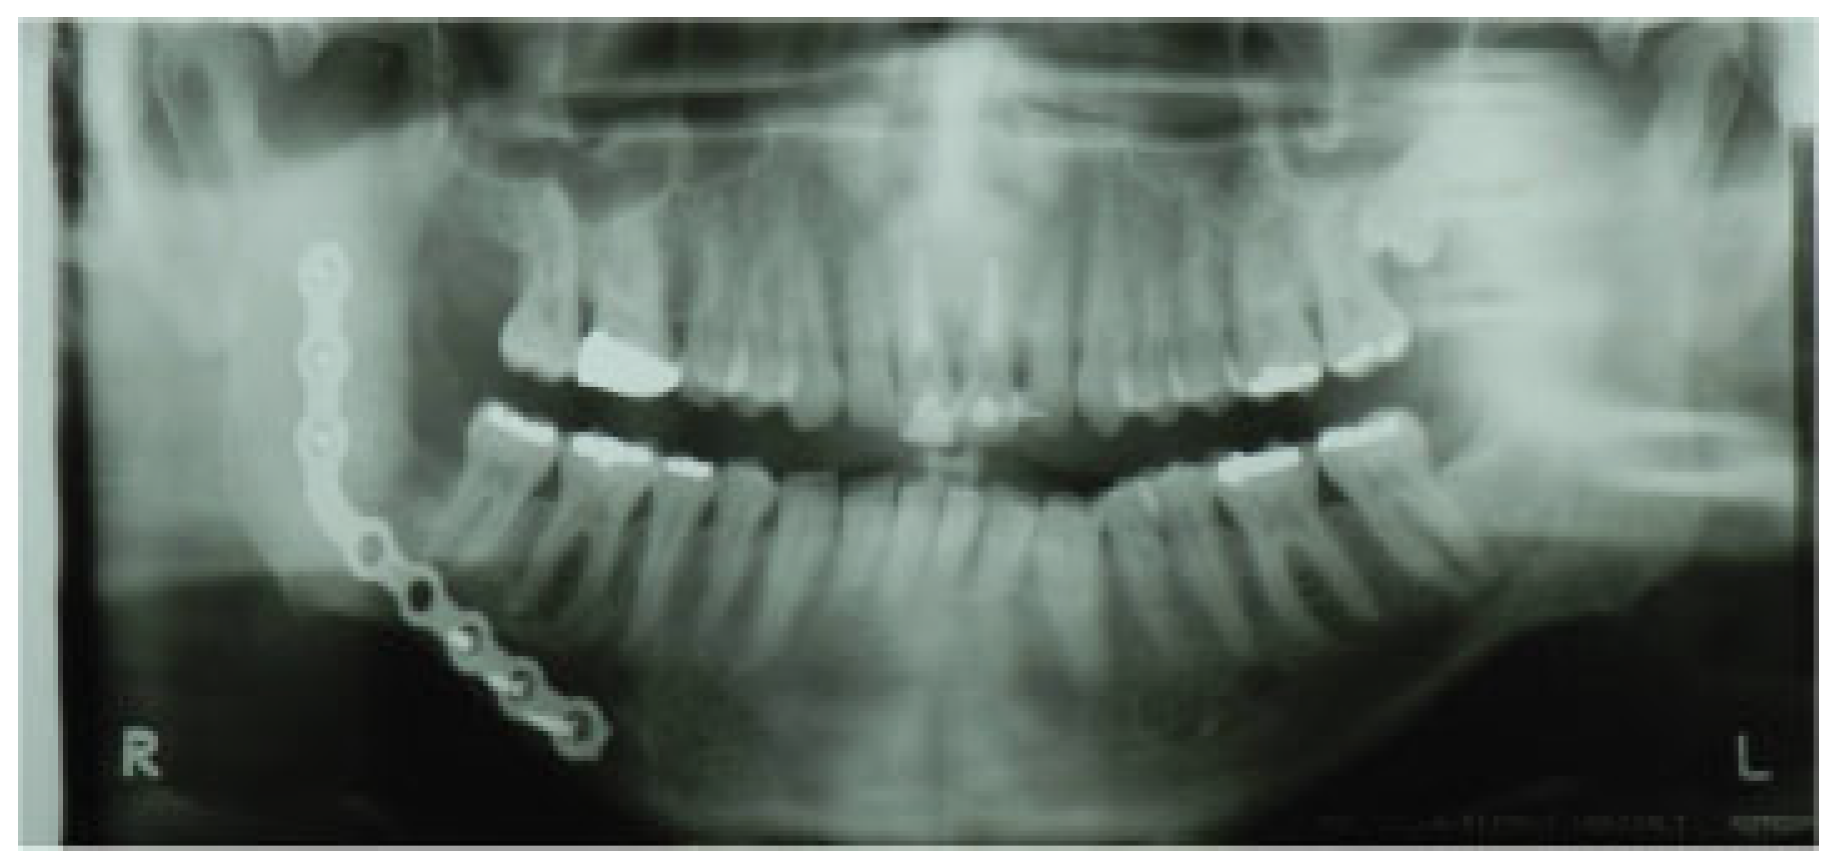

1.1. Case 1

1.2. Case 2

1.3. Case 3